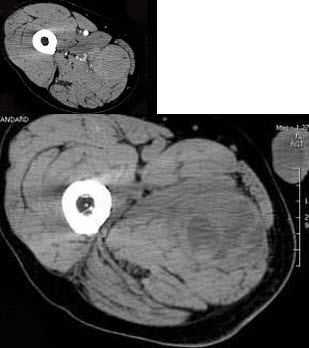

男,30岁,主诉右大腿肿块年余,逐渐增大,局部胀痛及压痛,根据图像表现,最可能的诊断是()A: 脓肿B: 血管瘤C: 脂肪瘤D: 横纹肌肉瘤E: 神经纤维瘤

男,30岁,主诉右大腿肿块年余,逐渐增大,局部胀痛及压痛,根据图像表现,最可能的诊断是()

- A: 脓肿

- B: 血管瘤

- C: 脂肪瘤

- D: 横纹肌肉瘤

- E: 神经纤维瘤